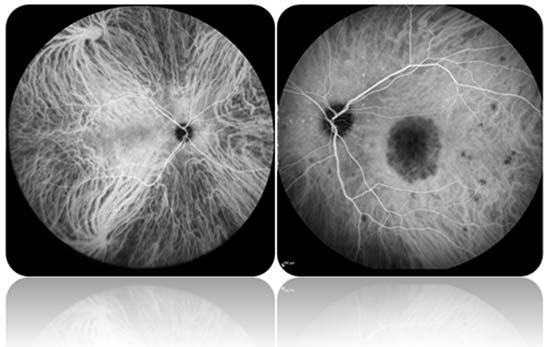

İndosiyanin Yeşili Anjiografisi

Koroid, retina altındaki damarlardan zengin tabakadır. İndosiyanin yeşili anjiografisi, göz bebekleri damlalar yardımı ile büyütüldükten sonra indosiyanin boyasının kol toplardamarlarından birine verilmesi sonrasında özellikle koroid ve aynı zamanda retinanın damarsal yapısının görüntülenmesi işlemidir.

Fotoğraflar ilk dakikada çekilmeye başlanır ve 30 dakika sonrasını da kapsayan kayıtlar alınır. Gebelerde ve iyot alerjisi olanlar da uygulanmaz. Çok nadiren ilaca karşı oluşan allerjik reaksiyonlara bağlı ciddi yan etkiler olabilir.